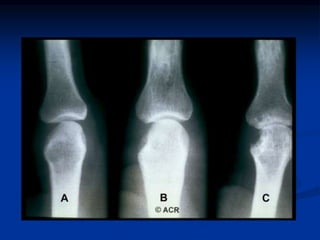

Radiographic Features

 Peri-articular osteopenia

 Uniform symmetric joint space narrowing

 Marginal subchondral erosions

 Joint Subluxations

 Joint destruction

 Collapse

 Ultrasound detects early soft tissue lesions.

 MRI has greatest sensitivity to detect

synovitis and marrow changes.